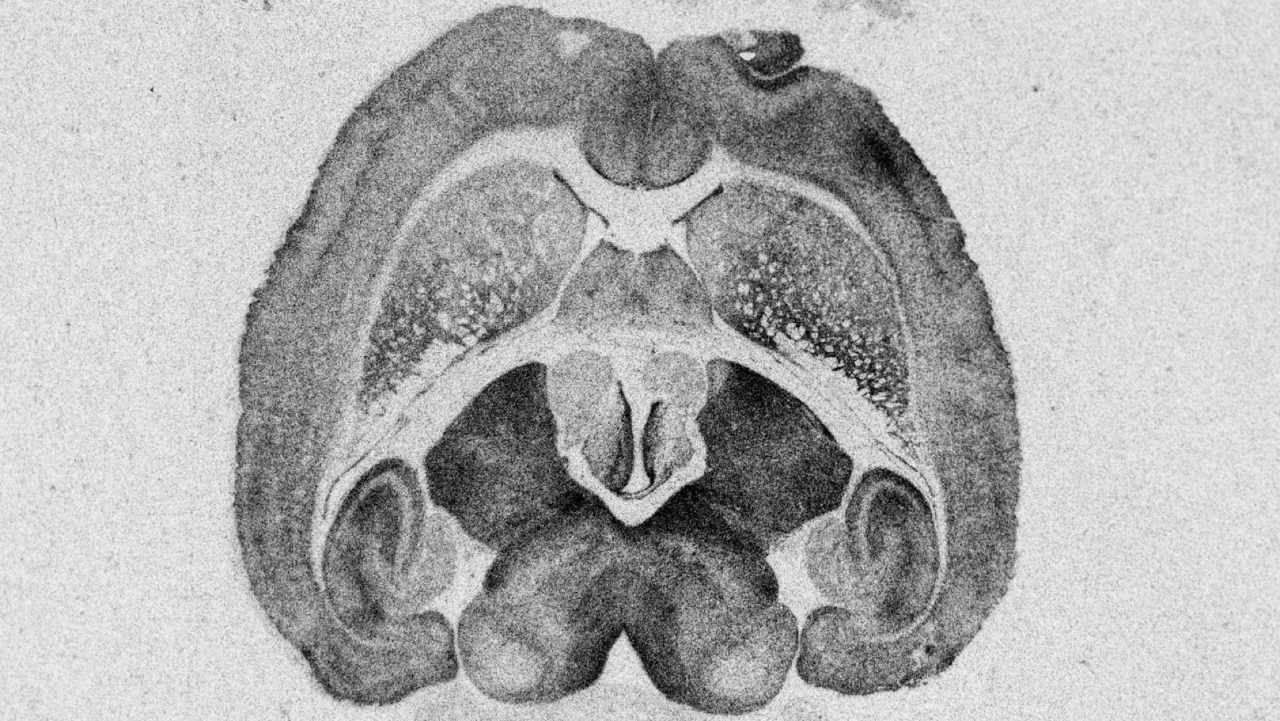

Chaque jour, nous travaillons sans relâche au développement de nouveaux traitements, qui peuvent faire une différence pour les personnes vivant avec des maladies du système nerveux central. Depuis des décennies, notre travail et notre engagement nous ont permis d’avancer, mais le chemin qui reste à parcourir est encore long. Le défi, immense, ne peut être laissé sans solution. Nous continuons à avancer dans la recherche d'une meilleure compréhension et de meilleurs traitements.